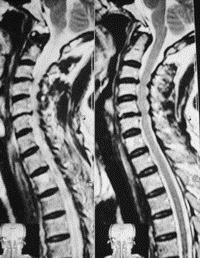

问题 病历摘要: 患者男性,67岁,因颈肩痛、臂痛併四肢乏力3年入院。体检:神清,颈项僵硬,双上肢、上臂外侧、三角肌区皮肤感觉减退,三角肌肌力Ⅲ级,肱二头肌反射亢进,肱三头肌反射亢进,双上肢霍夫曼氏征(+),双下肢皮肤感觉正常,肌力正常,膝反射、跟腱反射亢进,髌阵挛(+),踝阵挛(+)。 根据以上资料,最有可能的诊断是: 提示:X线片、MRI见图:

选项 A、椎间盘钙化 B、脊髓型颈椎病 C、交感型颈椎病 D、神经根型颈椎病 E、食管受压型颈椎病 F、后纵韧带骨化 G、椎动脉型颈椎病 H、混合型颈椎病

答案 B